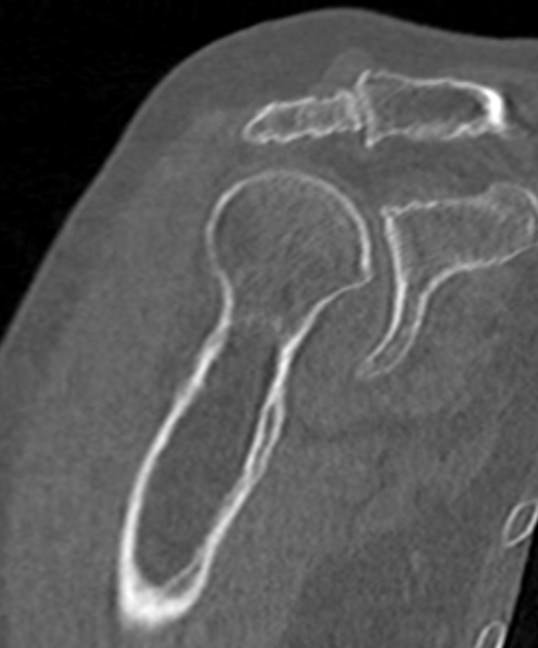

Плечевой сустав образован суставной впадиной лопатки и головкой плечевой кости и соединяет верхнюю конечность с плечевым поясом. Шаровидная форма сустава и отсутствие крепких связок обеспечивает большой объем движений верхней конечности. Но это же является и причиной травматизации, в частности, частых вывихов плечевого сустава.

Так как рентгеновские лучи хорошо поглощается костной тканью, метод КТ наиболее информативен именно для обследования костных структур. Кроме того, компьютерная томография отличается быстротой, безболезненностью и неинвазивностью (то есть не требует вмешательства в организм человека). Поэтому методика, в первую очередь, применяется для диагностики травматических повреждений – различных переломов, вывихов и подвывихов плечевого сустава.

Что показывает КТ плечевого сустава

- трещины, переломы (в т. ч. скрытые),образовавшиеся в полости сустава или в прилегающих тканях гематомы;

- остиомиелит, некроз головки плечевой кости;

- дегенеративные изменения: остеохондропатии, остеоартрозы, артрозы;